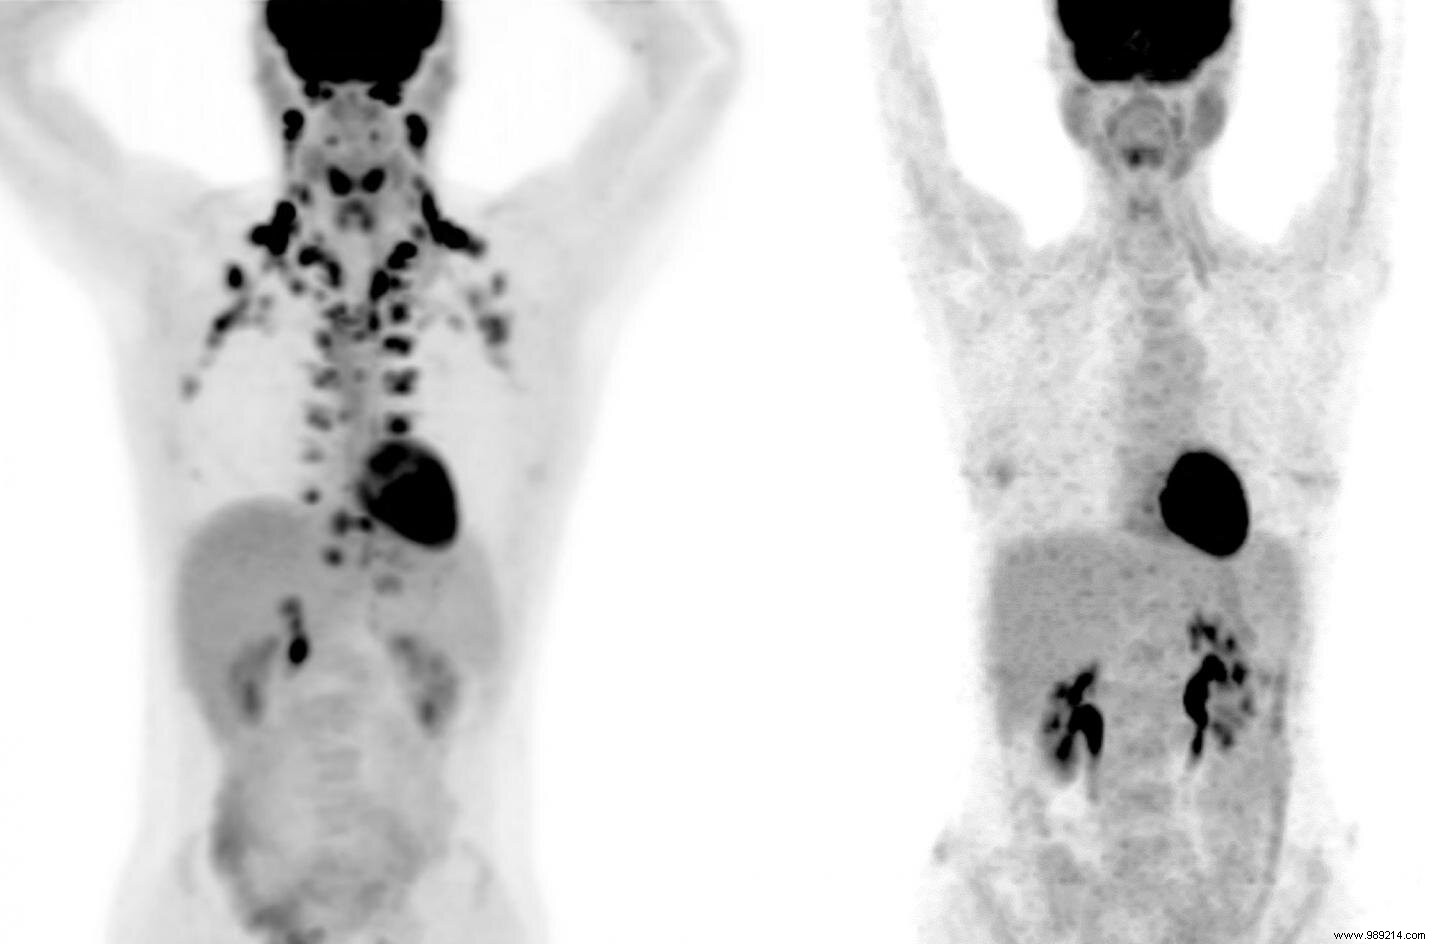

Studying brown fat poses challenges, as it is detectable only via PET scans, an expensive imaging technique involving radiation. "These scans are costly, and more critically, they expose people to radiation," explains Tobias Becher, the study's lead author. "We avoid using them on healthy individuals unnecessarily."

Analyzing 130,000 PET scans from over 52,000 patients, the team detected brown fat in about 10% of individuals. Notably, these people showed lower rates of several chronic conditions. For instance, type 2 diabetes affected just 4.6% of them, versus 9.5% in those without detectable brown fat. Abnormal cholesterol levels were seen in 18.9%, compared to 22.2% in the others.